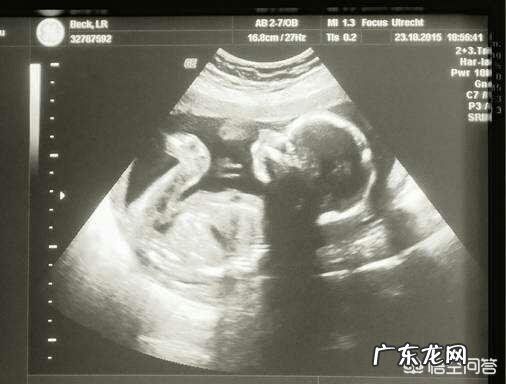

怀孕初期测量头臀长:也叫顶臀长,就是宝宝头顶部到臀部之间的长度,一般这个阶段胎儿还很小 。

【胎儿大小的判断标准是什么?】怀孕中晚期评估标准:等到怀孕中晚期,胎儿已经发育得差不多大时,就可以根据B超测量的胎儿双顶径、腹围、股骨长、头围等数据来综合评估胎儿的大小 。

孕31周胎儿大小正常吗?怀孕31周的胎宝宝,身长接近40cm,体重接近三斤半,皮肤颜色为深红色,而且呈皱缩状态 。在进行超声检查时,31周的胎宝宝双顶径参考值是7.7-7.9cm,头围参考值是28.2-28.9cm,腹围参考值是26.9-27.8cm,股骨长参考值是5.9-6.1cm 。但是由于胎宝宝的头围以及股骨长的数值和生长发育的状况、遗传因素等都有关系,而且不同的胎方位、头型,甚至不同的超声科医生进行检查,胎宝宝的股骨长、双顶径测量值也会出现偏差 。